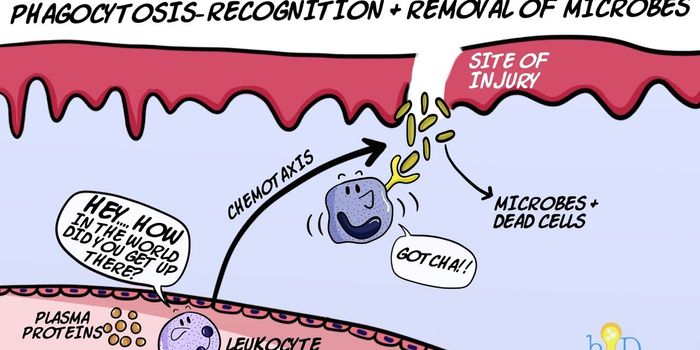

NOV 01, 2017VideosCells in the body have developed a variety of strategies toward removing harmful bacteria from the body. Phagocytosis is ...